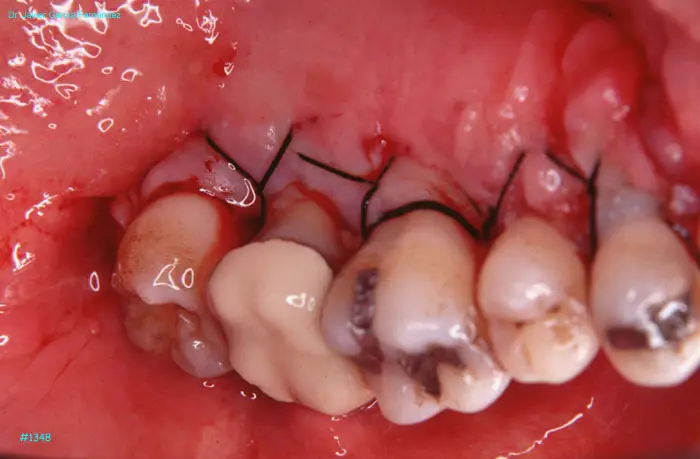

Atlas of Surgical Techniques in Periodontics. Chapter III. Atlas de Técnicas Quirúrgicas en Periodoncia